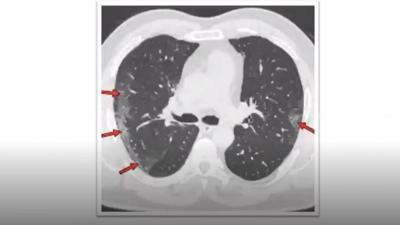

कोरोना वायरस फेफड़ों में सफेद धब्बे का कारण बनता है। रोगी के फेफड़ों में निमोनिया के लक्षण देखे जा सकते हैं। ये निशान कुछ में कम और कुछ में ज्यादा देखे जाते हैं।

कुछ रोगियों में, ये धब्बे फेफड़ों पर इस हद तक बढ़ते हैं कि फेफड़ों में वायुमार्ग अवरुद्ध हो जाते हैं। इसलिए, रोगी को अधिक ऑक्सीजन की आवश्यकता होती है। अक्सर मरीजों को वेंटिलेटर पर भी रखना पड़ता है।

इस फोटो में एक्स-रे को अलग तरह से देखा जाता है। जिसमें कोरोना वायरस के घाव पूरी तरह से दिखाई दे रहे हैं। सीटी स्कैन रिपोर्ट दाएं और बाएं ओर के फेफड़े को अलग-अलग वर्गों में विभाजित करती है और कई अंक देती है।

यदि स्कोर पांच है तो इसे हल्का माना जाता है और यदि यह 20 से ऊपर है तो स्थिति गंभीर है। इस प्रकार, कम से कम पांच से सात दिनों के बाद सीटी स्कैन द्वारा कोरोना वायरस का पता लगाया जा सकता है।